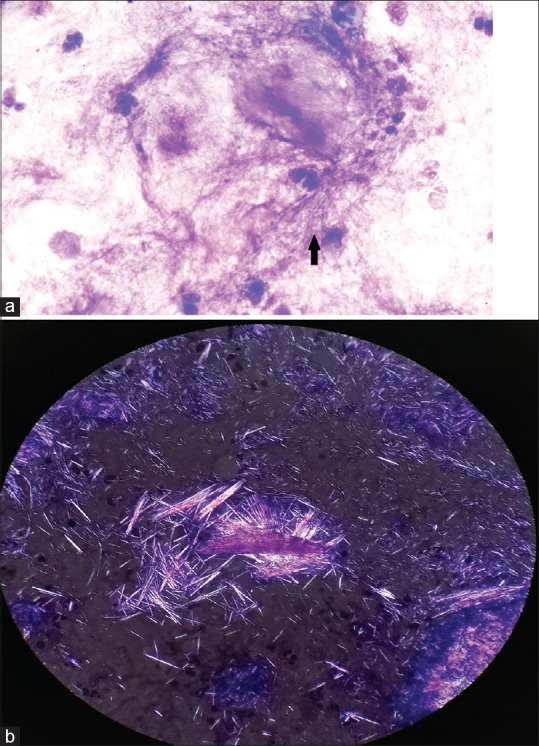

Complete blood count (Hb = 12.4 g/dl, TLC = 5500/μl, total platelets = 3 lacs/μl), liver function tests (SGOT = 26U/L, SGPT = 36U/L, ALP = 62U/L, Albumin = 3.5 g/dl, total bilirubin = 0.8 mg/dl), kidney function tests (serum creatinine = 0.8 mg/dl, urea = 16 mg/dl) were normal. Serum calcium (9 mg/dl) and parathyroid (PTH) levels (26 pg/ml, normal range = 10–65 pg/ml) were within normal limits. Rheumatoid factor was weakly positive but anti-cyclic citrullinated peptide (anti-CCP) came negative. Serum uric acid was 16.2 mg/dl. X-ray of the bilateral foot showed destruction of bilateral MTP joints and first IP joint of right foot. There were multiple juxta-articular joint erosions with sclerosis and overhanging margin [Figure 3]. Imprint smear from the discharging toothpaste-like material and fine-needle aspiration cytology from subcutaneous swellings revealed needle-shaped crystals in hematoxylin and eosin (H and E) stain [Figure 4a]. Von Kossa stain was negative for calcium. Negatively birefringent needle-shaped crystals were seen in polarizing microscopy [Figure 4b]. Ultrasonography of of abdomen and pelvis was normal. On the basis of clinical findings, biochemical results, radiological, cytological and polarized microscopic findings, a diagnosis of chronic tophaceous gout with extensive subcutaneous tophi was made. Indomethacin 75 mg twice a day and Allopurinol at 200 mg/day were added in the prescription. Prednisolone was tapered to 5 mg. After 10 days of intake of 200 mg of allopurinol serum uric acid came down to 7.6 mg/dl along with improvement in joint pain. The patient was lost to follow-up subsequently.

Figure 4.

(a) 100X, hematoxylin and eosin (H and E) stain: Imprint smear showing needle-shaped crystals. (b) Negatively birefringent crystals in polarized microscopy

Diagnosis of cutaneous gout can be done by seeing amorphous crystalline material in histopathology and negatively birefringent needle-like crystals in polarized microscopy. Gouty arthritis is diagnosed based upon raised serum uric acid and X-ray findings, first MTP involvement, juxta-articular erosions with sclerotic margins and overhanging edges and relative preservation of joint spaces in early stage of the disease.[9] In our case, there was destruction of bilateral MTP joints and first IP joint of right foot along with multiple juxta-articular joint erosions, sclerosis, and overhanging margin.

Gouty arthritis involving large joints can be confused with rheumatoid arthritis and tophi with calcinosis cutis. However, both entities can be differentiated by serological, biochemical, and radiological investigations. In our patient, rheumatoid arthritis with calcinosis cutis was ruled out due to normal serum calcium and PTH levels along with negative anti-CCP and von Kossa stain. The diagnosis of gouty arthritis was made basing upon raised serum uric acid and X-ray findings and tophaceous gout was diagnosed by imprint smear showing needle-shaped crystals and negatively birefringent crystals in polarizing microscopy.